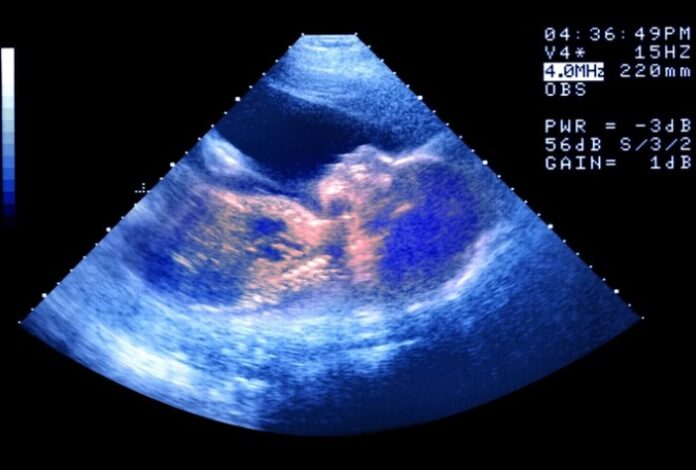

No dia 26 de julho, nasceu em Ohio, nos Estados Unidos, Thaddeus Daniel Pierce, bebê gerado a partir de um embrião congelado em 1994. Com mais de 30 anos entre a fertilização e o nascimento, ele estabeleceu o recorde mundial do embrião humano mais antigo a resultar em parto bem-sucedido.

O embrião foi criado na década de 1990 para Linda Archerd, que teve quatro embriões gerados por fertilização in vitro (FIV). Um deles deu origem a uma menina, hoje com 30 anos, enquanto os outros três foram criopreservados.